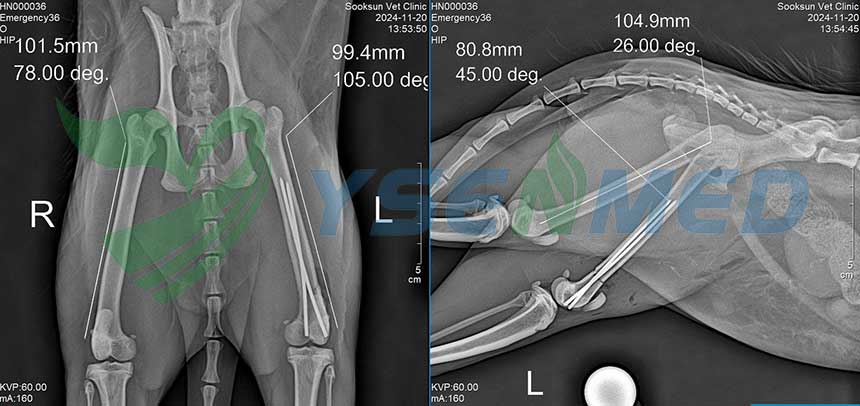

A Thai vet clinic digitizes its analog x-ray system with YSENMED YSFPD-M1717V VET flat panel detector, and the vet is very satisfied with the quality images and our after-sale service.